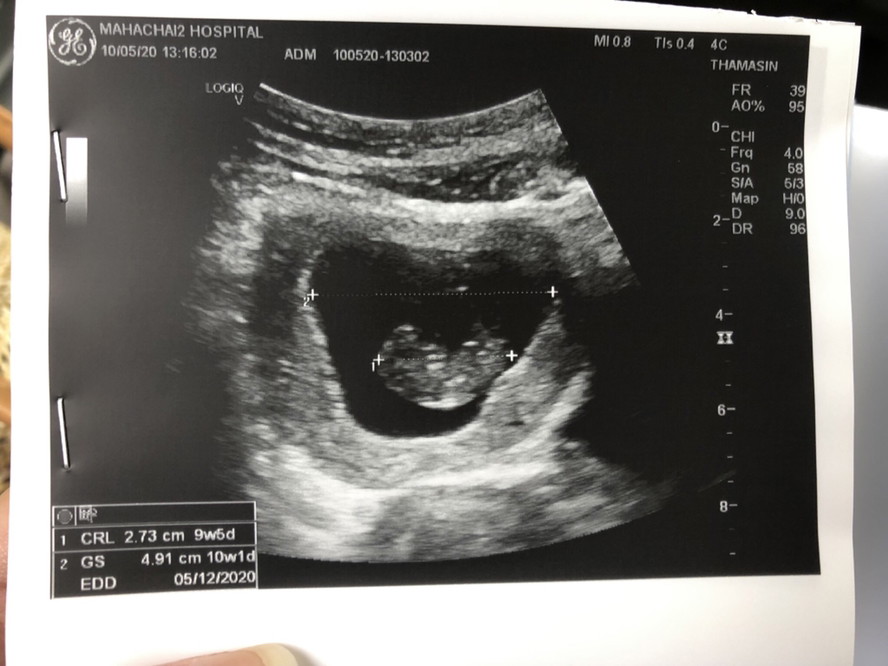

ขอดูใบซาวหน่อยจ้า เเล้วกำหนดคลอดวันที่เท่าไรกันค่ะ

วันที่ 5 ธ.ค. จ้า